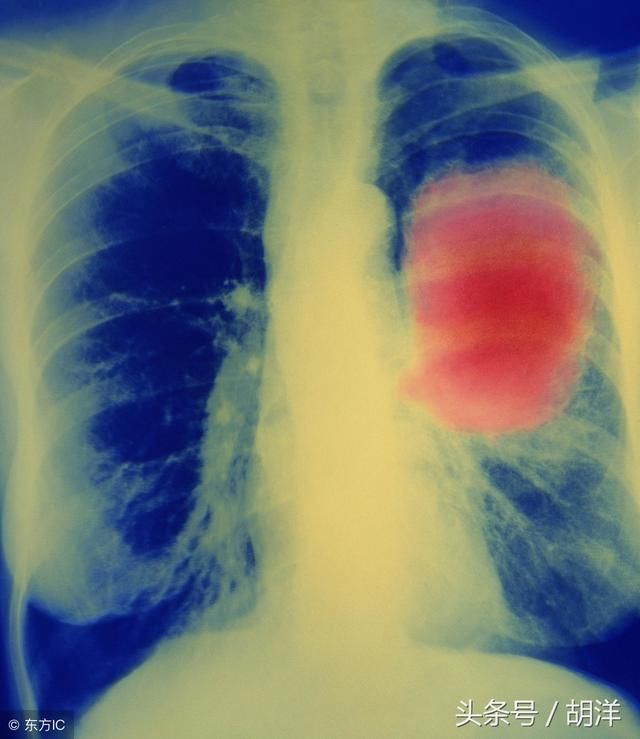

肺癌早期呼吸道可能出现的症状,此外还会出现如图骨关节痛,肩背痛等肺